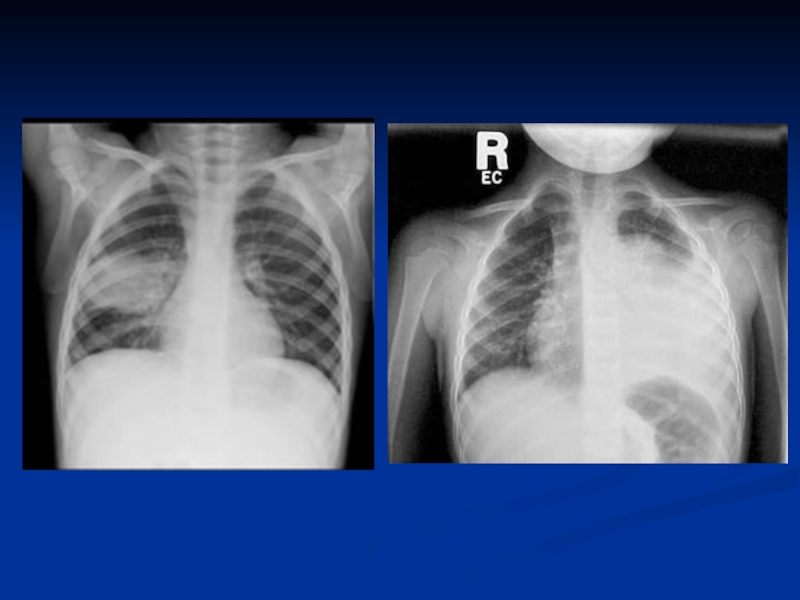

рентгенограмма: инфильтраты легочной ткани, чаще с обеих

сторон; усиление легочного рисунка в перифокальных участках.

рентгенограмма: инфильтраты легочной ткани, усиление легочного рисунка в перифокальных участках.